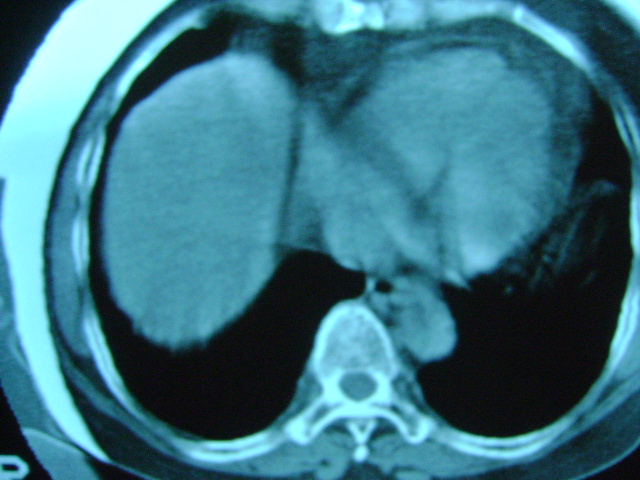

朋友的母亲,56y,咳嗽三个月,感觉左肺门不对,请大家给点意见

心功能不全肺淤血

肺内应该存在感染